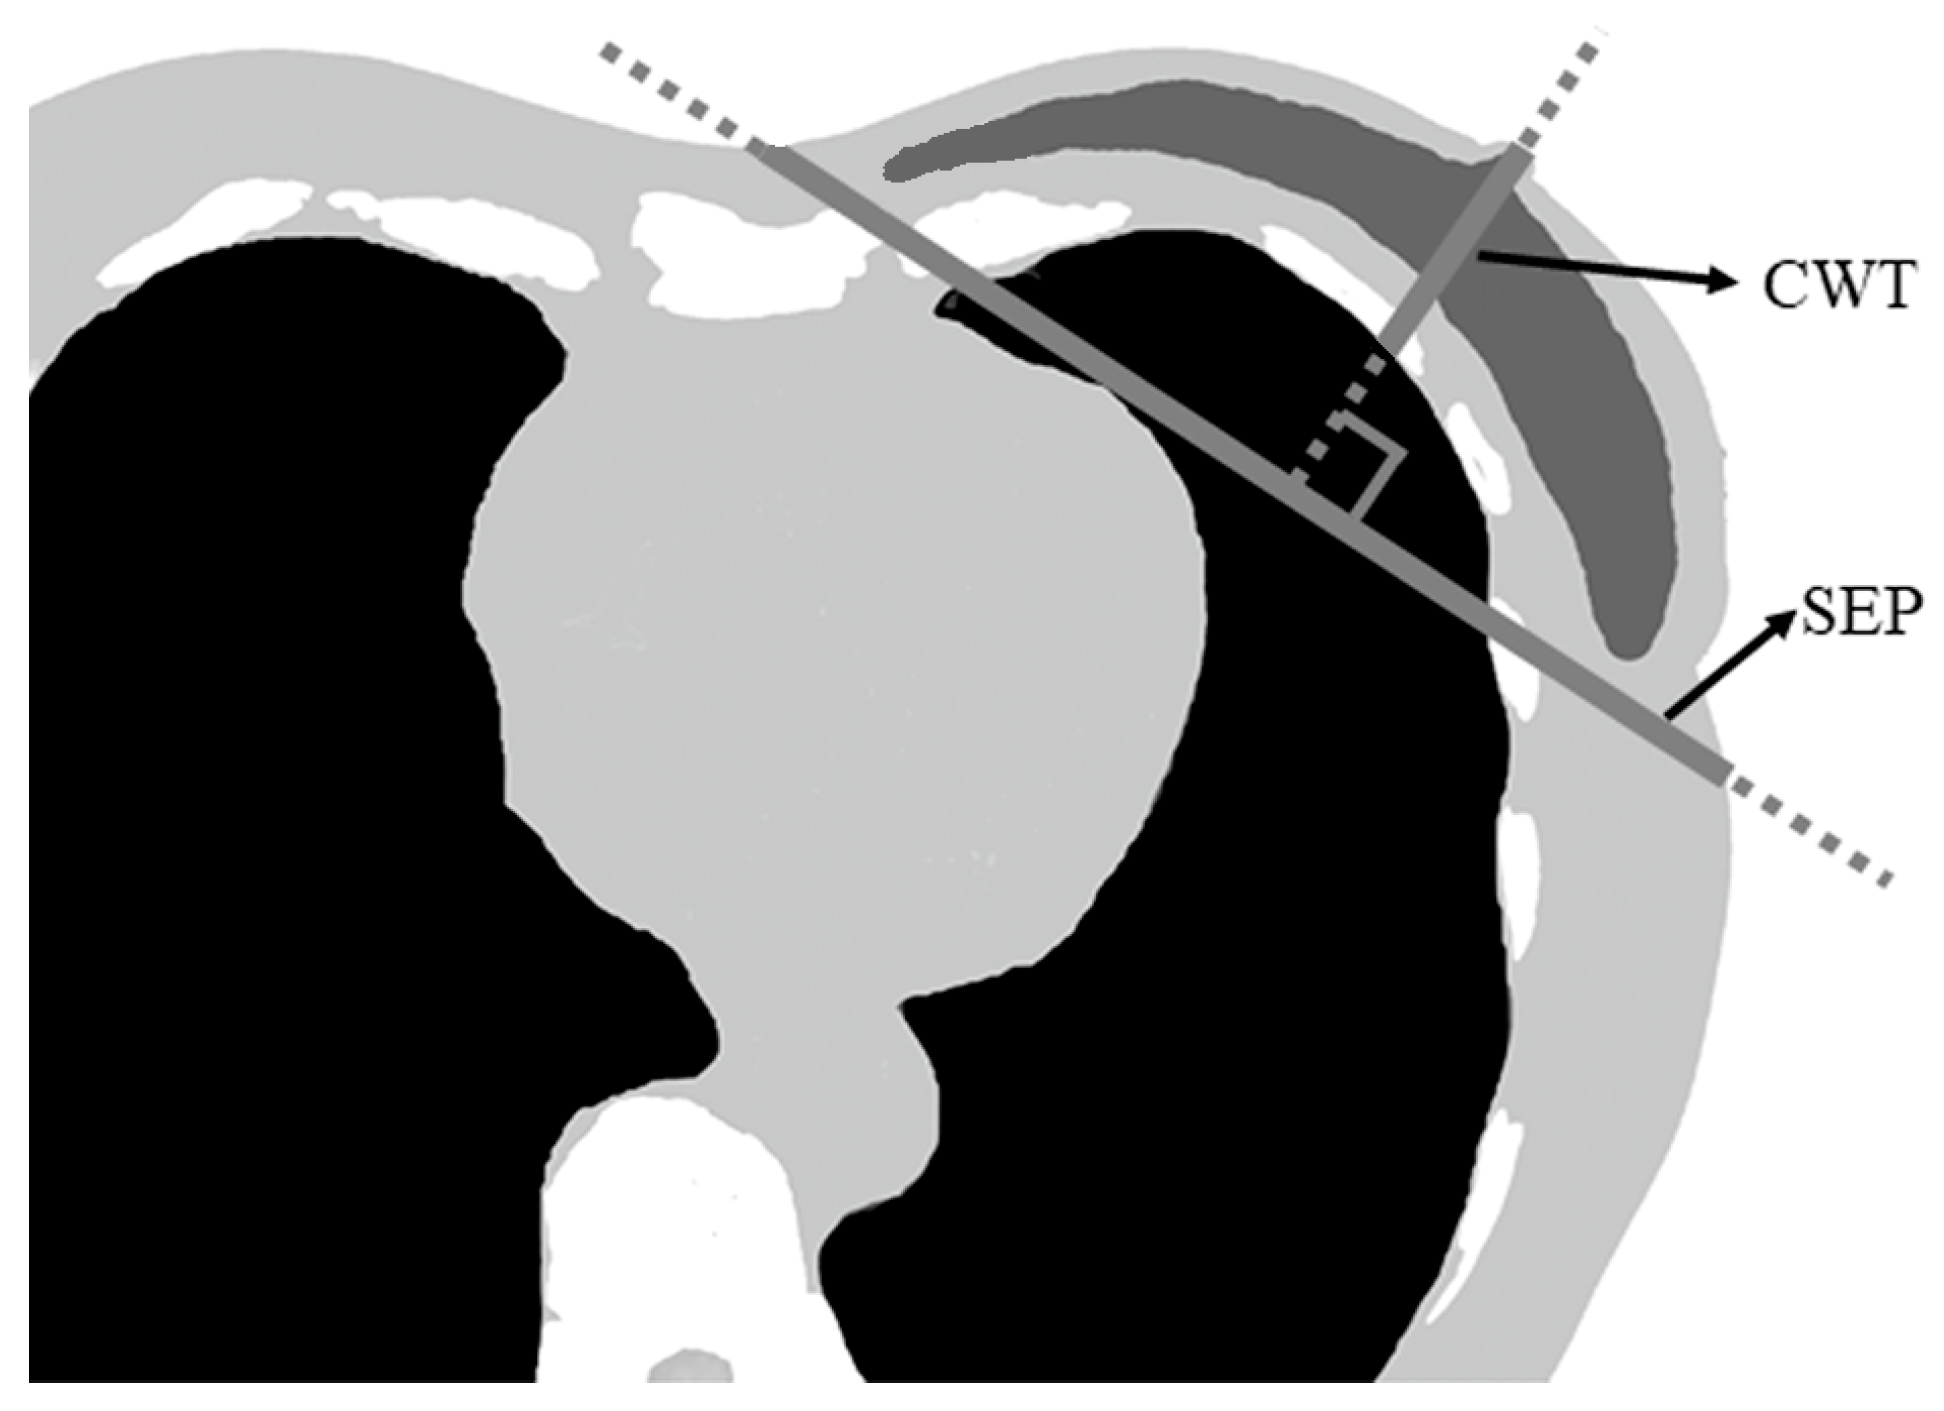

| Chest wall thickness (median (IQR), cm) | 6 (5.1–6.8) | 0.335 a | <0.001 |

| Separation (median (IQR), cm) | 19 (17.1–20.2) | 0.290 a | <0.001 |